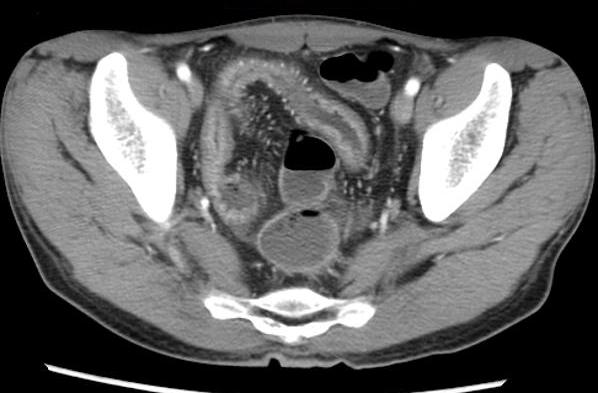

Image de

hypervascularisation " Comb sign " et epaissisement

de la paroi du ileon se voyait si nette sur les

coupe TDM axiale |